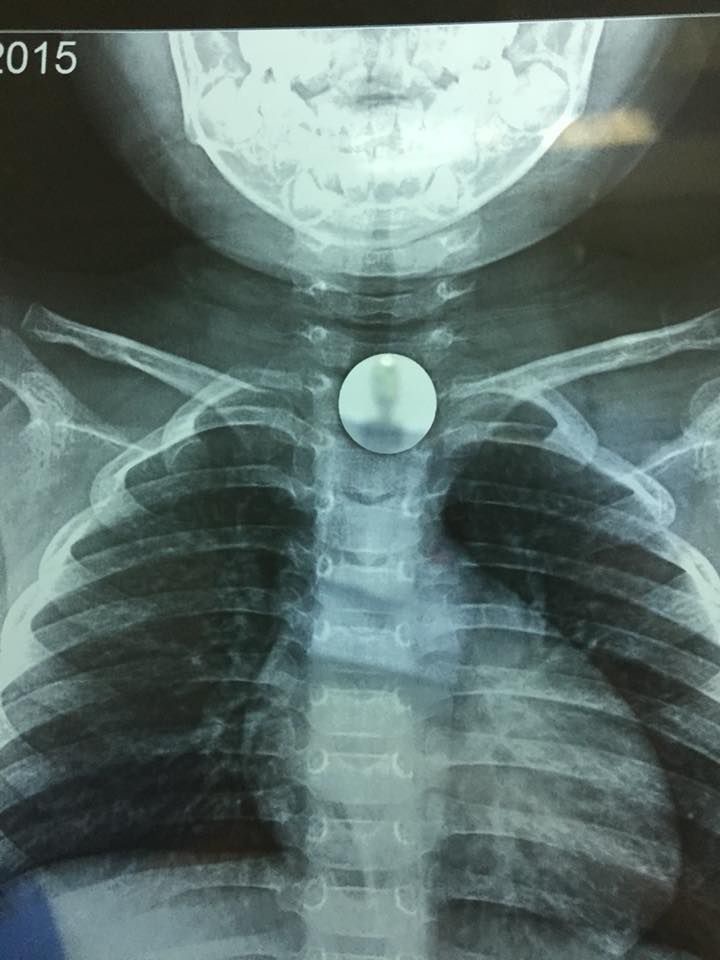

Sau khi tiếp nhận, các bác sĩ Bệnh viện đa khoa Đức Giang đã nhanh chóng chỉ định chụp phim X-quang vùng ngực - cổ để xác định vị trí dị vật. Hình ảnh X-quang cho thấy dị vật là một hình tròn nằm ở vị trí ngang giữa cổ. Dị vật mắc kẹt có cạnh tròn xung quanh nên không gây tổn thương niêm mạc.

Hình ảnh đồng xu mắc ở ngang cổ của bé gái